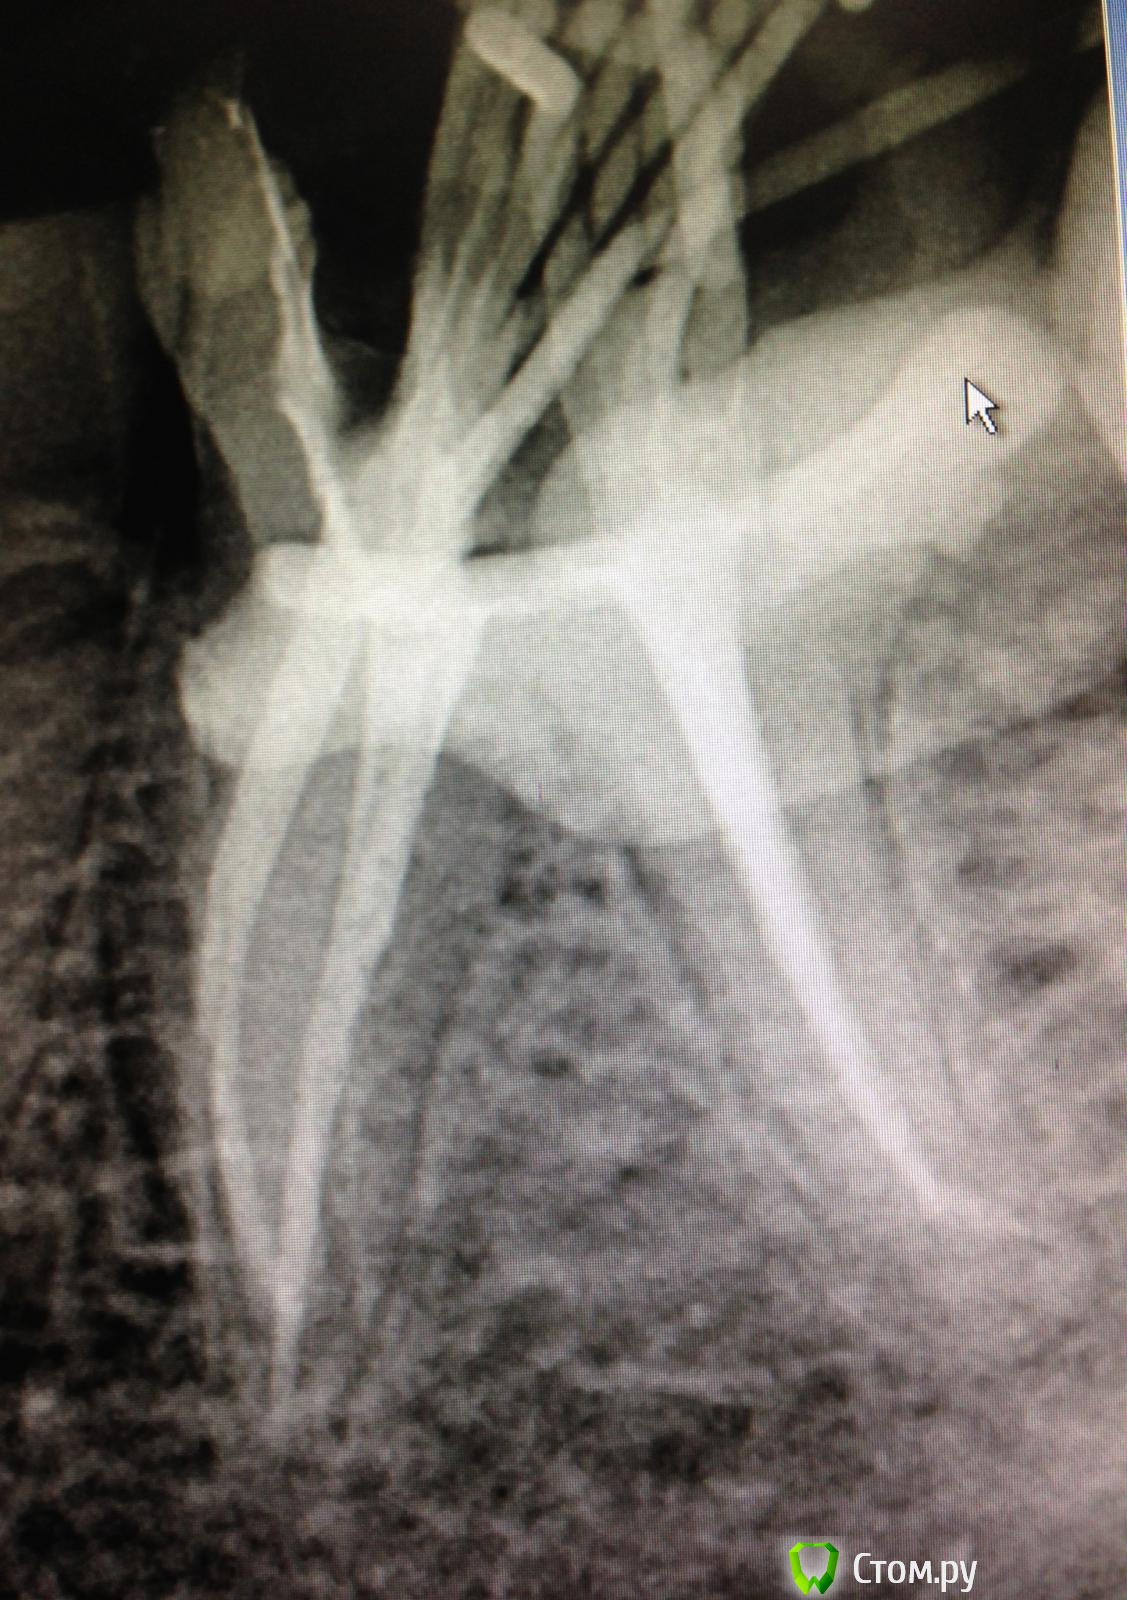

SSTi Опубликовано 2 сентября, 2014 Автор Поделиться Опубликовано 2 сентября, 2014 Кейс позора) В общем история такова. Это один из моих первых пациентов, если не первый. Только начал работать. Наконечник толком не умел держать. Ну в общем зеленый-зеленый. Диагноз не помню(пульпит или периодонтит). Это сделал я, признаюсь(года 2 назад) )))без коффера, метазоном, огромная залипуха и супер штифт на 2 мм в канале. 1 пустой. Естественно это дало обострение. Боль при накусывании и все дела. Переделал с удовольствием. Планируется вкв и мк. 3 Ссылка на комментарий